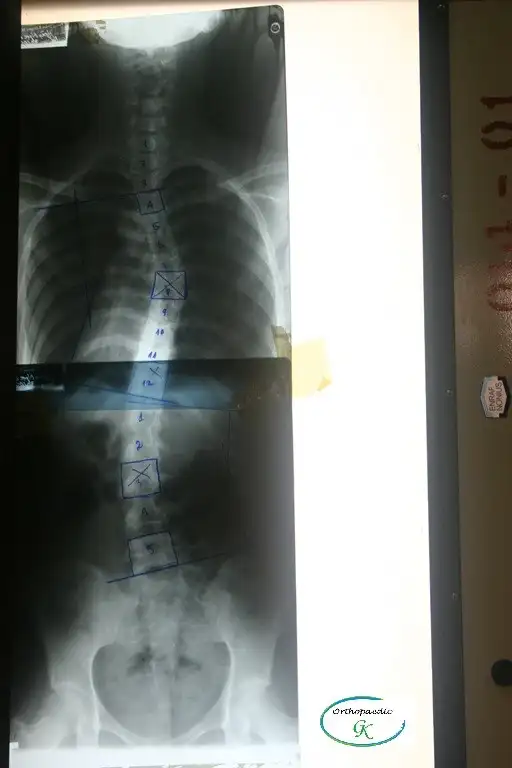

Điều trị vẹo cột sống

Có nhiều nguyên nhân khác nhau dẫn đến vẹo cột sống, bao gồm di chứng của bại liệt, bại não, tật nứt đốt sống, dị tật đốt sống và chấn thương hệ thần kinh-cơ-xương, nhưng trong phần lớn các trường hợp, không xác định được nguyên nhân cụ thể. Trường hợp này được gọi là vẹo cột sống vô căn (nghĩa là không rõ nguyên nhân).

Vẹo cột sống vô căn (Idiopatic Scoliosis): là tình trạng cột sống bị cong, vẹo mà không rõ nguyên nhân Đây là dạng thường gặp nhất trong các loại vẹo cột sống có cấu trúc cố định (tức là cột sống cong thật, không phải do tư thế). Bệnh thường bắt đầu ở trẻ em hoặc thanh thiếu niên và có thể nặng dần lên cho đến khi cơ thể ngừng phát triển xương (khoảng sau tuổi dậy thì). (Stagnara, 1988.)

Việc đeo Áo chỉnh hình (orthosis) thường có thể điều trị vẹo cột sống, tuy nhiên nếu góc cong của cột sống vượt quá 45º thì sẽ rất khó điều trị bằng phương pháp này. (Thomas M. Gavin và cộng sự, 2001)

Điều trị bằng nẹp chỉnh hình được khuyến nghị cho những bệnh nhân chưa trưởng thành về mặt xương khớp và có độ cong tiến triển từ 25º đến 45º (theo góc Cobb), trong khi phẫu thuật cố định cột sống được chỉ định cho các trường hợp có độ cong vượt quá 45º. (Thomas M. Gavin và cộng sự, 2001)